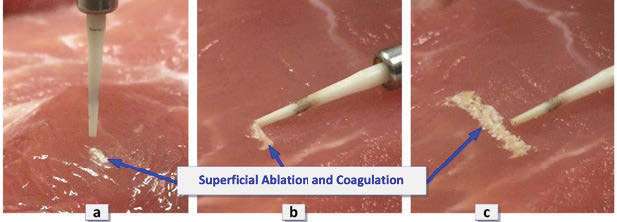

Laser handpiece LightScalpel PN LS9002-02 was fitted with a 0.25 mm spot size diameter hollow waveguide ceramic Al2O3 perio tip (distal OD=0.5mm, ID=0.3mm, working length 10mm) Light- Scalpel PN LS9005-05. The fluence level at the tip’s distal aperture exceeds 26 J/cm2 during each individual SuperPulse, which is sufficient for efficient ablation of the soft tissue[24] and bacterial biofilms.[25] The laser beam out of the perio tip diverges at approximately 14º, which is important for delivering laser energy to the walls of the sulcus and the implant during the closed peri-implantitis treatment procedure. Laser tissue interaction for different tip orientations (normal and parallel to the tissue) is illustrated in Figure 3. Both orientations produce efficient ablation and coagulation of the soft tissue.

Simulated sulcular debridement is shown in Figure 4. For epithelial crest ablation, the perio tip is oriented normal to the surface of the soft tissue as illustrated in Figures 3A and 4C. For sulcular and peri-implant pocket debridement applications, the perio tip is oriented parallel to the walls of the pocket, as indicated in Figures 3B and 3C and Figures 4A and 4B. Constant airflow through the hollow core of the tip pushes the sulcular debris and fluids (blood, saliva, and irrigation) out of the way of the laser beam; airflow also prevents the clogging of the hollow tip. Laser energy from the tip, directed at the surface of the tissue at the shallow angles of a few degrees, ablates/coagulates the surface of the soft tissue. When moved sideways, laser energy ablates/coagulates a strip of approximately 0.5 mm-1 mm width (see Figure 3B). Multiple passes of the tip produce multi-mm wide strip of superficial ablation and coagulation (see Figures 3C and 4B). During intra-pocket lasing, laser energy is also partially directed at the surface of the implant, which results in ablation of the biofilms off the surface of the implant, and its bacterial decontamination provided[25] SuperPulse fluence exceeds approximately 3 J/cm2. Laser energy is also reaching the infected, granulated tissue at the bottom of the sulcular pocket.